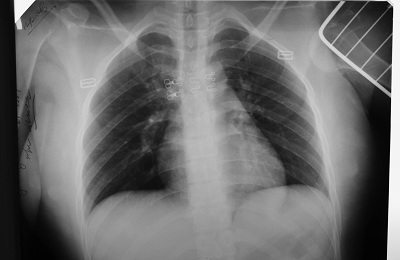

Довольно часто туберкулез на раннем этапе развития становится рентгенологической находкой при очередном прохождении флюорографии при профосмотре.

image

Ограниченный туберкулезный процесс в верхней доле правого легкого

В целом, в начале заболевания состояние заболевших детей и взрослых будет будет мало отличаться от здорового человека. Единственное обследование при данных формах туберкулеза, которое действительно способствует раннему обнаружению туберкулеза легких — это флюорографическое обследование (а еще лучше обзорная рентгенография органов грудной клетки). Именно поэтому флюорография легких входит во все медосмотры и профосмотры.